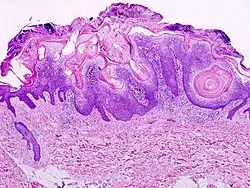

Micrograph of a seborrheic keratosis (H&E stain, scanning magnification)

Visual diagnosis is made by the "stuck on" appearance, horny pearls or cysts embedded in the structure. Darkly pigmented lesions can be challenging to distinguish from nodular melanomas.[10] Furthermore, thin seborrheic keratoses on facial skin can be very difficult to differentiate from lentigo maligna even with dermatoscopy. Clinically, epidermal nevi are similar to seborrheic keratoses in appearance. Epidermal nevi are usually present at or near birth. Condylomas and warts can clinically resemble seborrheic keratoses, and dermatoscopy can be helpful to differentiate them. On the penis and genital skin, condylomas and seborrheic keratoses can be difficult to differentiate, even on biopsy.

A study examining over 4,000 biopsied skin lesions identified clinically as seborrheic keratoses showed 3.1% were malignancies. Two-thirds of those were squamous cell carcinoma.[11] To date, the gold standard in the diagnosis of seborrheic keratosis is represented by the histolopathologic analysis of a skin biopsy.[12]